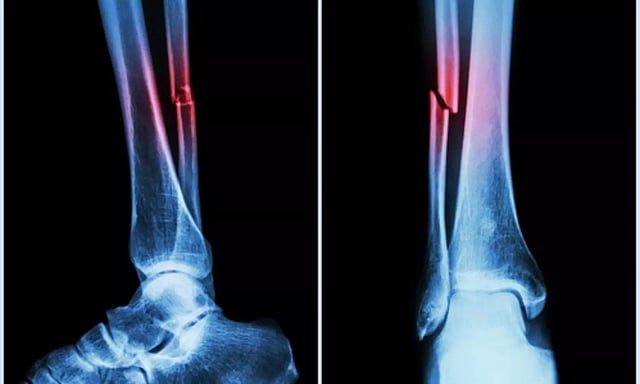

Bone Fracture Illustration (IANS)

NEW DELHI: Integrating Artificial Intelligence (AI) with gait analysis can greatly improve treatments for people with fractures, suggests a study on Wednesday.

Gait analysis can help doctors gauge how an individual stands and walks, especially in the case of a fracture.

Together with AI, early gait analysis can be key in providing insights into the injury's impact on locomotion and recovery which can help personalise and improve rehabilitation strategies.

Using AI can help predict "post-injury complications such as infection, malunion, or hardware irritation among individuals with lower extremity fractures", said the researchers in the paper, published in the Journal of Orthopaedic Research.